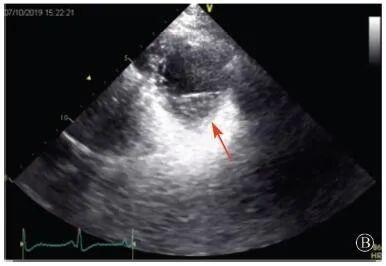

患者入院后無特殊不適,心率70次/min,血壓110/60 mmHg,心功能Ⅱ級。查血常規(guī):血紅蛋白139 g/L,白細胞7.39×109/L,血小板221×109/L。尿常規(guī)、便常規(guī)+潛血均正常。生化:丙氨酸氨基轉(zhuǎn)移酶38 U/L,白蛋白47 g/L,鉀3.9 mmol/L,肌酐(酶法)65 μmol/L,總膽固醇3.52 mmol/L,低密度脂蛋白膽固醇2.08 mmol/L。CK:1256→487 U/L,CK-MB 9.7→3.8 μg/L,cTnI 85.90→68.50 pg/ml。N末端B型利鈉肽原70 pg/ml。CK同工酶電泳:肌酸激酶MM質(zhì)量100.0%(此時CK-MB已正常)。血沉1 mm/第1小時,高敏C反應蛋白1.61 mg/L;補體:C3 0.876 g/L,C4 0.174 g/L。免疫球蛋白:IgG 9.52 g/L,IgA 1.73 g/L,IgM 0.62 g/L。血清蛋白電泳未見M蛋白。糖化血紅蛋白5.1%。乳酸(運動前)1.1 mmol/L,乳酸(運動中)6.6 mmol/L,乳酸(運動后)7.8 mmol/L。肌炎抗體譜:抗PM-SCL75(+),余均(-)。心電圖:aVL、V5、V6導聯(lián)T波倒置(圖2)。冠狀動脈CT未見明顯異常。超聲心動圖:左室舒張末內(nèi)徑55 mm,左室收縮功能減低,心尖部、左室壁普遍運動減低,以左室下后壁為著,左室下后壁肌小梁明顯增多可見隱窩,疏松層與致密層之比為1.7;左室射血分數(shù)(雙平面)45%;右冠狀動脈開口6.5 mm,開口處未見明確瘤樣擴張(圖3)。

協(xié)和疑難︱第67例:臨床表現(xiàn)胸痛伴肌酸激酶升高

A:胸骨旁長軸平面,左室舒張末內(nèi)徑略增大,室壁無明顯增厚;

B:胸骨旁左室短軸切面心尖水平,可見心肌肌小梁增多,其內(nèi)可見隱窩(箭頭所示)

圖3 患者入院后超聲心動圖